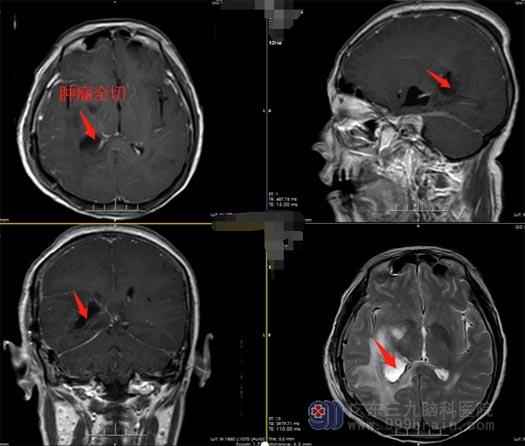

楼大姐入住了广东三九脑科医院神经外五科,王国良主任带领治疗团队为患者制定了手术方案,取得楼大姐及家属手术后,由王国良主刀,在全麻下为楼大姐进行右侧侧脑室后角脑膜瘤切除术,手术过程顺利,术后恢复良好。

▲术后